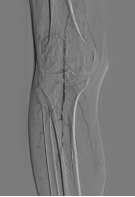

患者林某,80岁,于20年前诊断为“2型糖尿病”,因“右足破溃、疼痛10天”以“2型糖尿病性足溃疡和周围血管病”第一次住院。经治疗破溃无好转。出院后坏疽逐渐加重,近日再次入院。经下肢血管彩超检查诊断为下肢动脉粥样硬化闭塞症,患者因下肢动脉闭塞缺乏血流供应,伤口不愈合,拟行截肢术。为改善患趾血流,在征得患者与家属同意后,内分泌科组织于DSA下进行手术,术中造影见患者右股动脉起始部狭窄,中段串珠样狭窄,收肌管处股动脉闭塞,膝下胫前动脉、胫后动脉、腓动脉无显影。术中给予股动脉支架植入,胫前动脉和腓动脉球囊扩张术。术后造影显示股动脉、腘动脉血流通畅,胫前及胫后动脉血流通畅,足背动脉血流好。

图一 患者术前血管血流情况